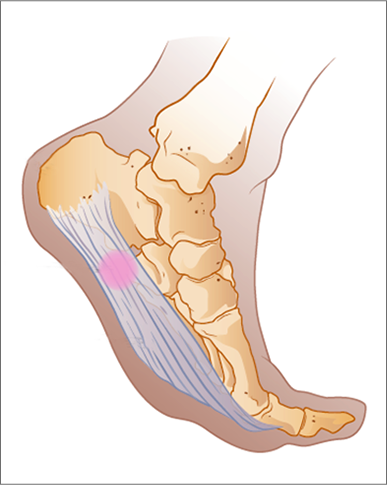

족저 근막염은 발바닥에 위치한 족저근막에 염증이 생기는 질환으로, 발꿈치에 통증을 유발합니다. 주로 하루 중 첫 번째 걸음에서 통증이 심하게 나타나며, 장기간 서 있거나 걷는 것에 어려움을 겪을 수 있습니다. 과도한 운동이나 비만, 잘못된 신발 착용 등으로 발병할 수 있습니다.

족저 근막염 증상 5. 발바닥 아랫부분의 통증

발꿈치 외에도 발바닥 아랫부분에 통증이 발생할 수 있습니다. 통증은 주로 발꿈치에서부터 발바닥 중앙까지 느껴지며, 장시간 걷거나 서 있을 때 더욱 심해집니다.